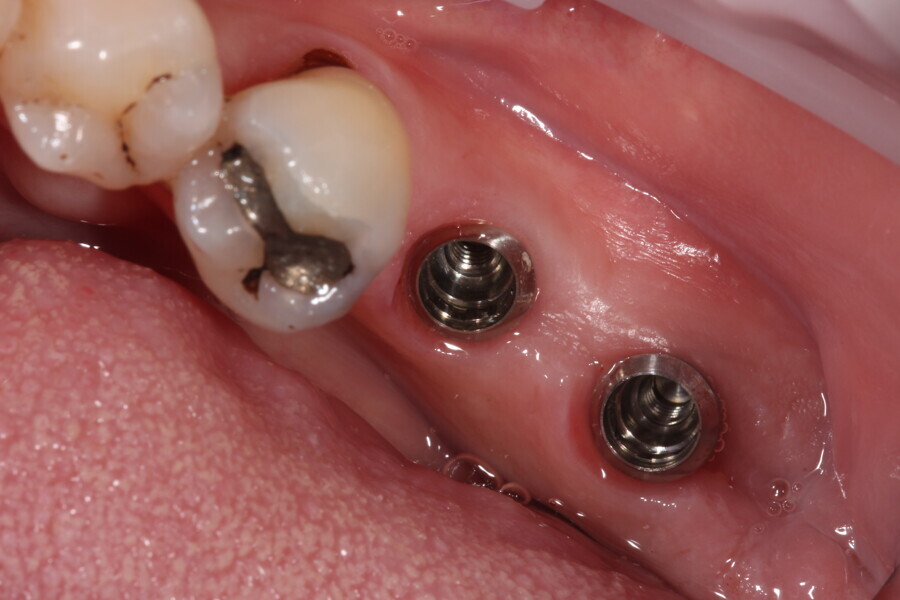

Fig. 11: Tissue level implants.